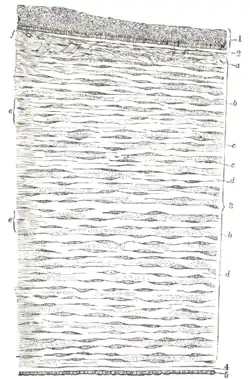

Vertical section of human cornea from near the margin. (Corneal endothelium is #5, labeled at bottom right.) | |